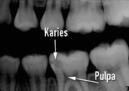

Ett hål bildas

Det är svårt för syran att lösa upp den hårda emaljen, men när ett hål väl bildats går det fortare. Syran fräter sig sedan in i det mjukare dentinet. Om hålet inte behandlas kan bakterierna tränga längre in i tanden så att den innersta delen, pulpan, blir inflammerad. Inflammationen kan i vissa fall fortsätta ut i käkbenet och ge skador även där.